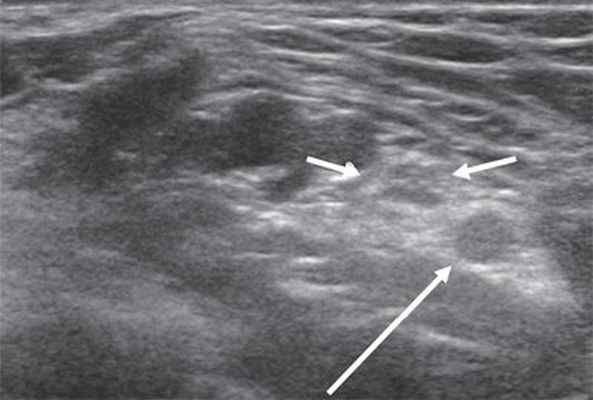

Седалищный нерв - самый большой из периферических нервов в организме человека. Фактически он состоит из двух крупных стволов: кнаружи находится общий малоберцовый нерв, медиально - большеберцовый нерв. Седалищный нерв выходит из полости малого таза через большое седалищное отверстие под грушевидной мышцей.

Уже в ягодичной области нерв доступен визуализации, необходимо только правильно определиться с частотой используемого датчика: при достаточной мышечной массе целесообразно применять датчики с частотой 2-5 МГц, если мышечная масса в ягодичной области не выражена, можно использовать датчики с большей частотой - 5-9 МГц. В области ягодичной складки седалищный нерв располагается близко к широкой фасции бедра, смещается латерально и далее лежит под длинной головкой двуглавой мышцы бедра, располагаясь между ней и большой приводящей мышцей (рис. 4).

В дистальных отделах бедра, чаще в верхнем углу подколенной ямки, нерв делится на две ветви: более толстую медиальную - большеберцовый нерв и более тонкую латеральную - общий малоберцовый нерв. Именно с этой области лучше всего начинать ультразвуковое исследование седалищного нерва и его ветвей.